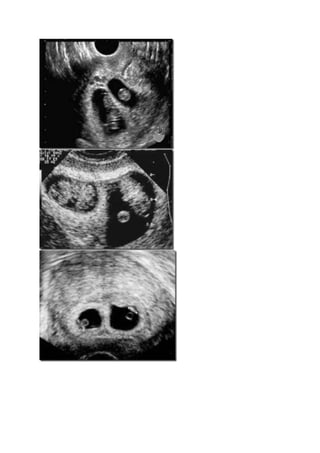

Diagnosa dengan ultrasonografi lebih mudah dilakukan yaitu dengan mengukur diameter

ventrikel lateral dan ketebalan cortex cerebri serta membandingkan ukuran kepala dengan

ukuran thorax dan abdomen.